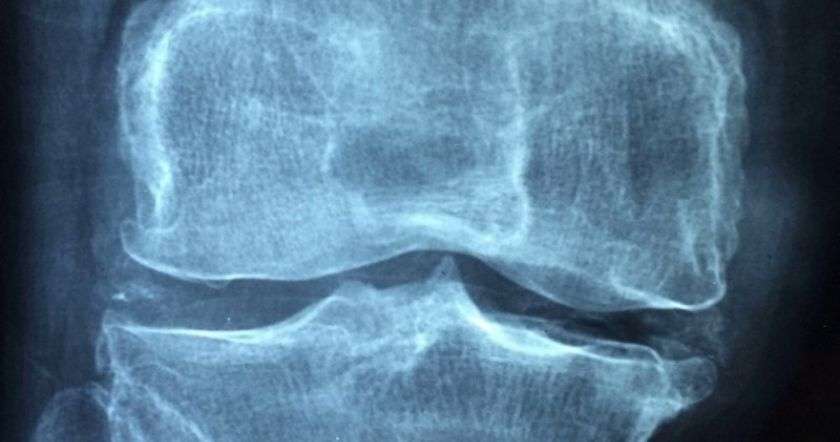

В этом обсервационном исследовании более 1,1 тыс. человек с высоким риском ОА, но без его рентгенологического подтверждения, наблюдались в течение десяти лет. По результатам у энергично тренирующихся людей на 30% снижалась вероятность развития ОА. Однако ученые подчеркивают, что данное значение нельзя считать статистически значимым.